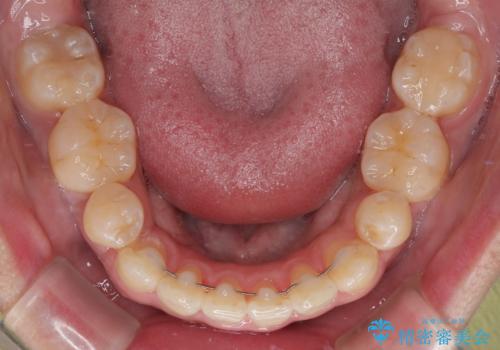

前歯のデコボコを抜歯矯正で改善した症例|目立ちにくい審美装置を使用

- 「歯並び全体のデコボコをきれいに整えたい」とのご希望で、20代男性の患者様が来院されました。

特に前歯部の叢生(歯の重なり)が強く、見た目だけでなく歯磨きのしにくさも気にされていました。

診査の結果、上下前歯に強い叢生が認められ、歯をきれいに並べるためのスペースが明らかに不足していました。

無理に歯を並べると、前歯が前方に突出するため、抜歯によるスペース確保が必要と判断しました。

上下左右の小臼歯を抜歯し、歯列を整えるためのスペースを確保

左下は第二小臼歯に根管治療歴があったため、左下のみ第二小臼歯を抜歯しアンカースクリューを併用

それ以外の部位は第一小臼歯を抜歯

矯正中の見た目を気にされていたため、プラスチックブラケット+コーティングワイヤーを使用した、目立ちにくい審美矯正装置を選択しました。